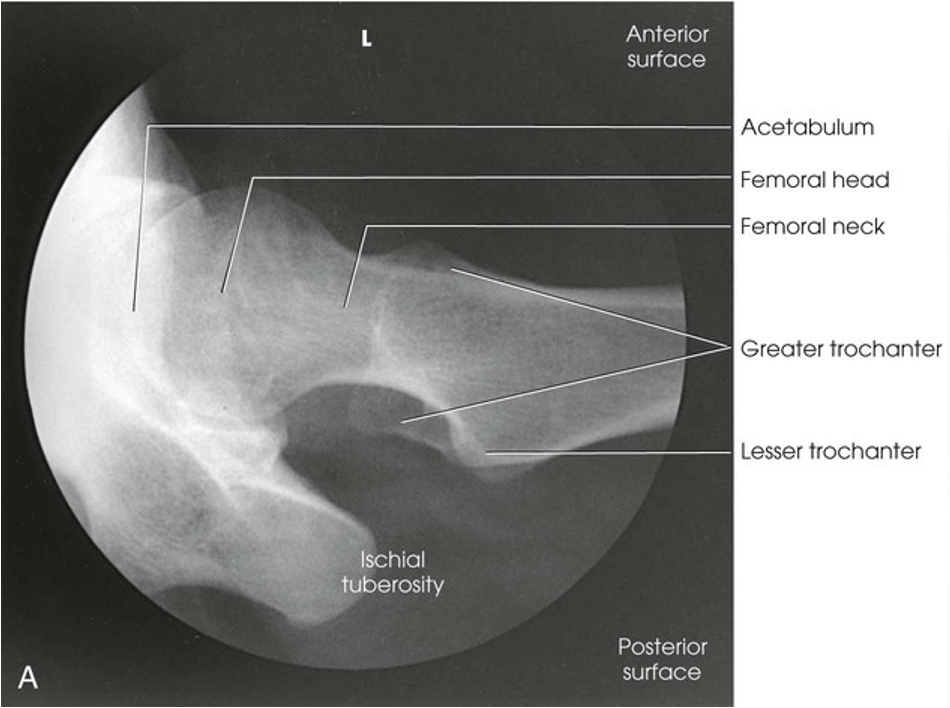

Lateral Projection; Hip; Lauenstein and Hickey Methods (Lauenstein Method)

Lateral Projection; Hip; Lauenstein and Hickey Methods (Lauenstein Method) (Labeled)

Lateral Projection; Hip; Lauenstein and Hickey Methods (CR & SS)

Perpendicular through the hip joint, which is located midway between the ASIS and the pubic symphysis for the Lauenstein method and at a cephalic angle of 20-25 degrees and an additional 1 inch (2.5 cm) more inferior for the Hickey method

The resulting image shows a lateral projection of the hip, including the acetabulum, the proximal end of the femur, and the relationship of the femoral head to the acetabulum

Lateral Projection; Hip; Lauenstein and Hickey Methods (Eval Criteria)

• Evidence of proper collimation

• Hip joint centered to the radiograph

• Hip joint, acetabulum, and femoral head

• Femoral neck overlapped by the greater trochanter in the Lauenstein method

• With cephalic angulation in the Hickey method, the femoral neck free of superimposition

• Soft tissue and bony trabecular detail